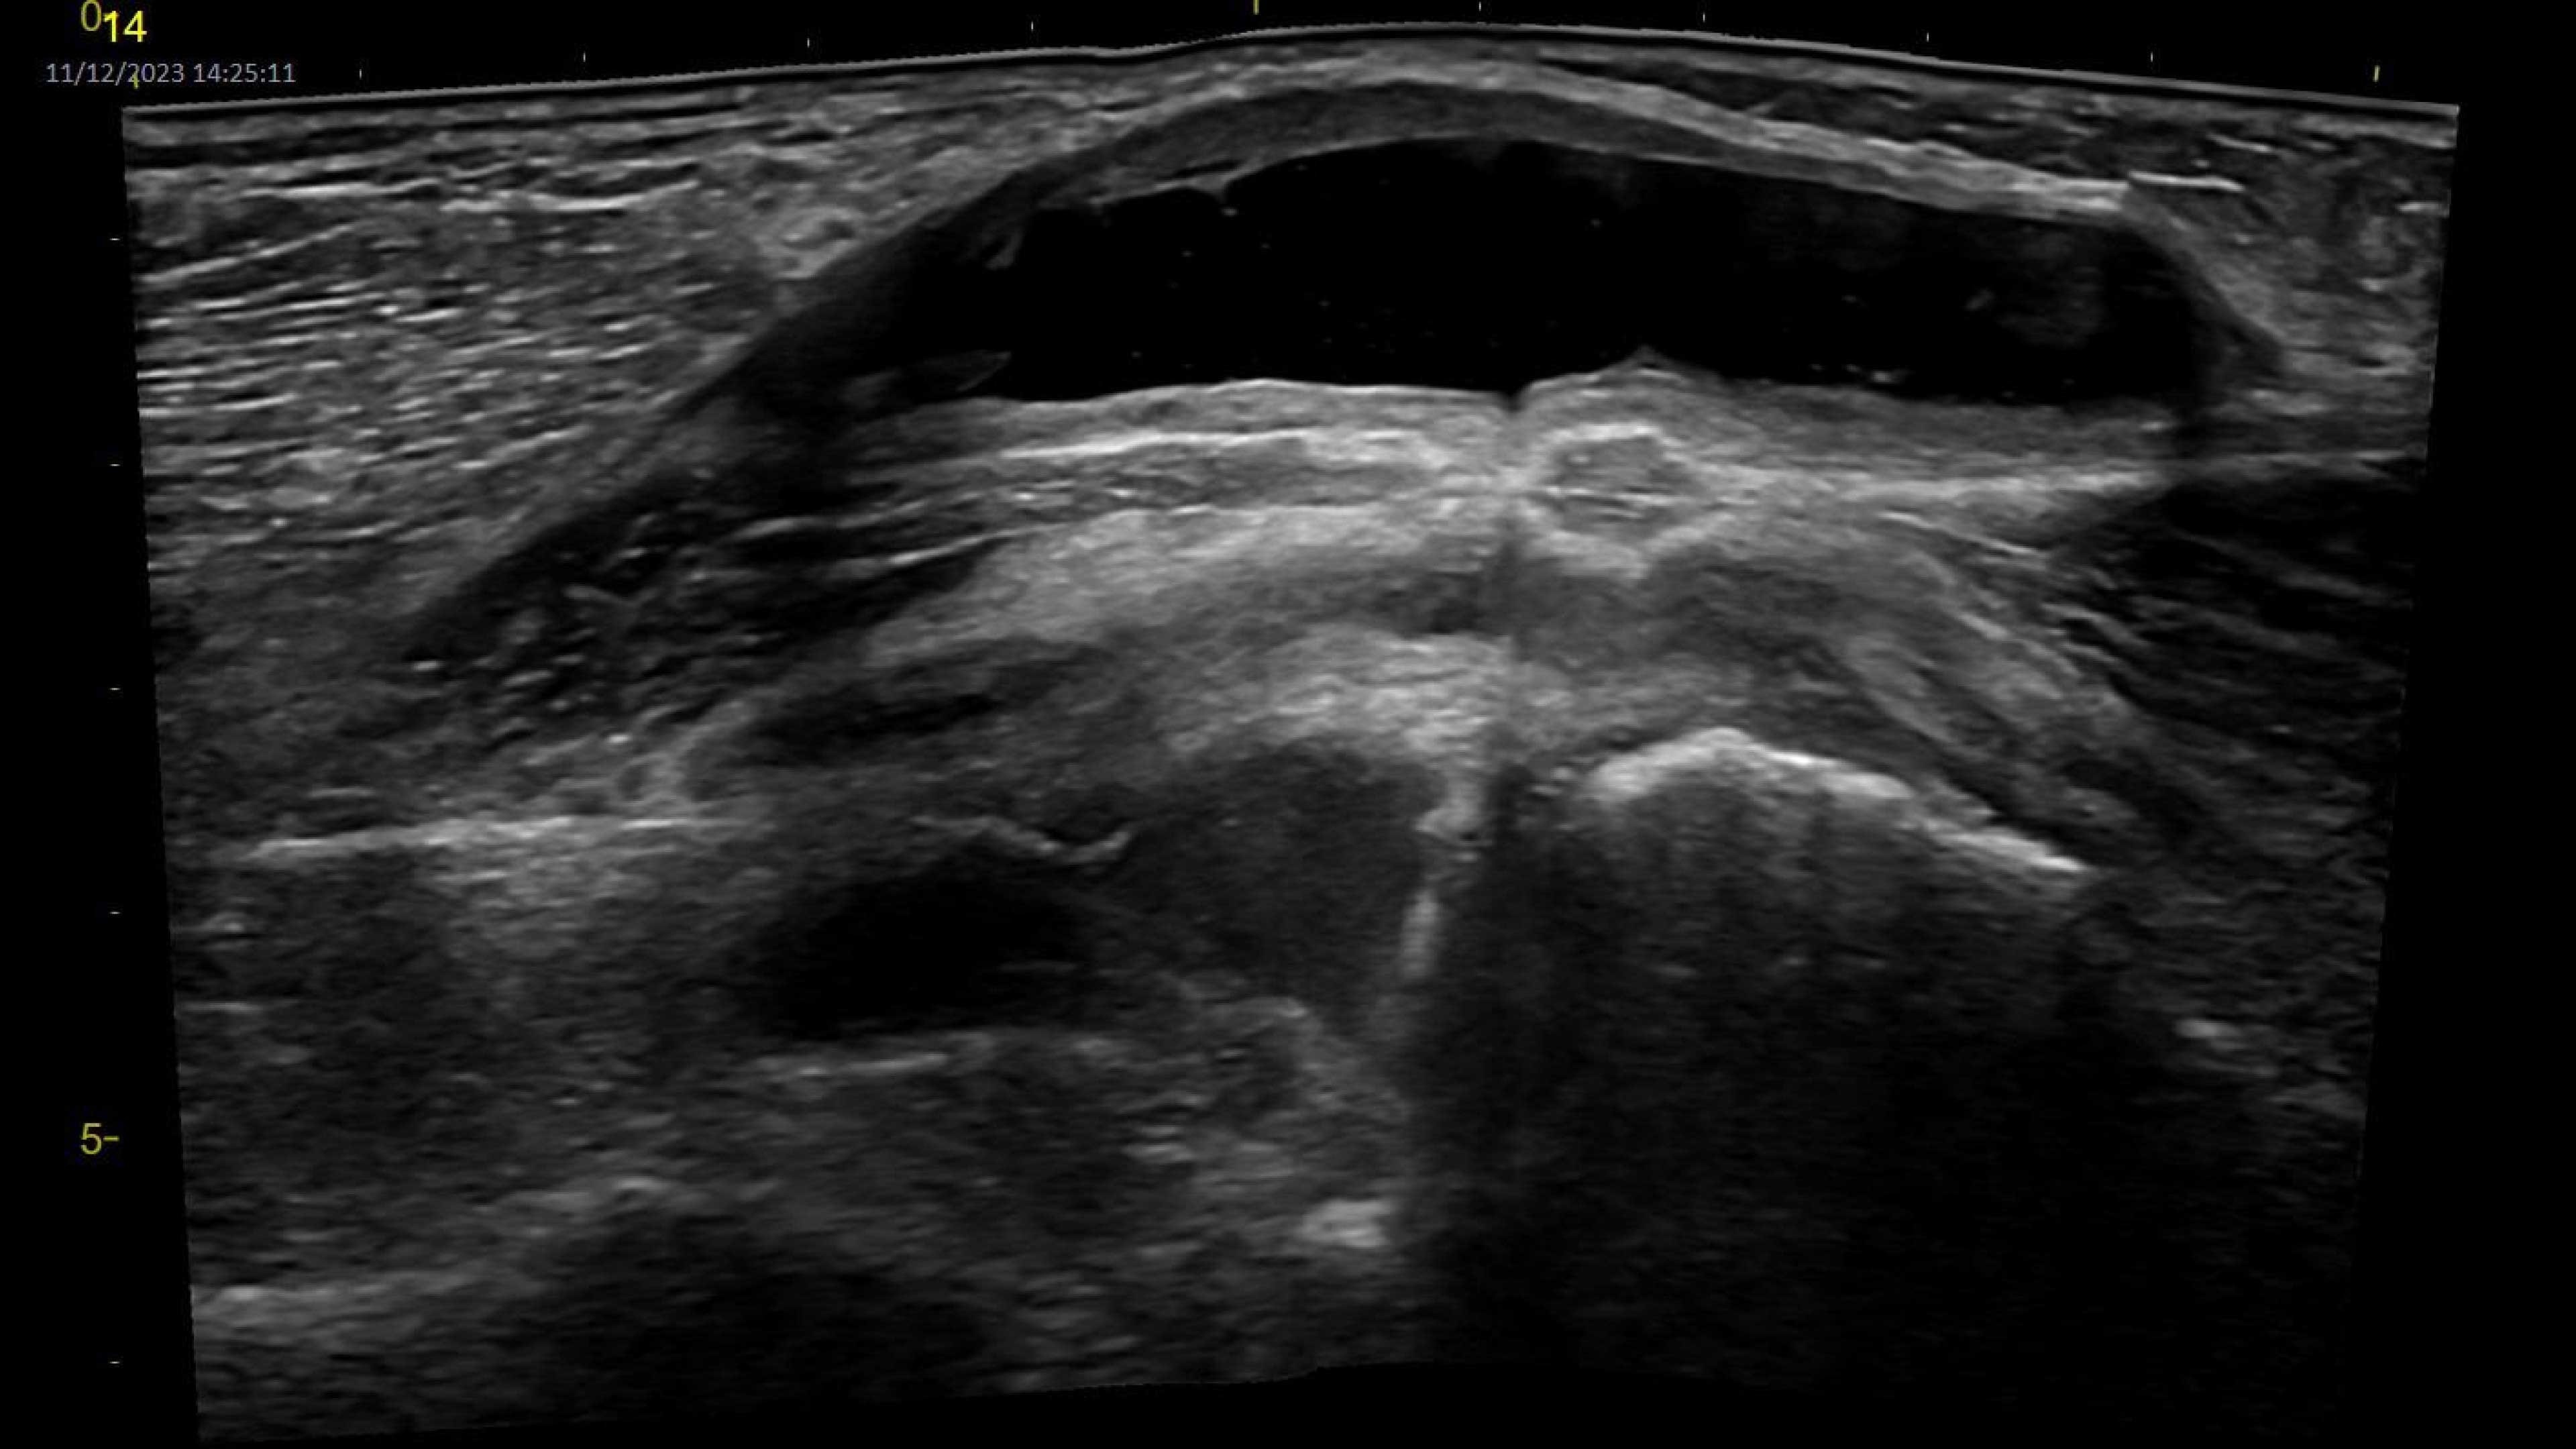

Emergency medicine

Enables assessments for a variety of anatomy all with a single device. Supports deep and shallow scanning with seamless data connectivity.